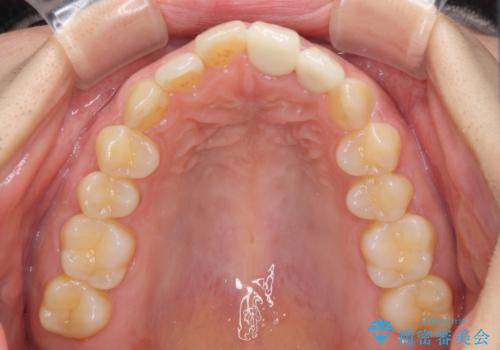

仮歯装着の時点で自然な見た目となり、オールセラミッククラウンを装着した際には、まるで自分の歯のようと喜んでくださいました。

長年変色を気にしており、もっと早くに治療を行えば良かったとおっしゃっていました。